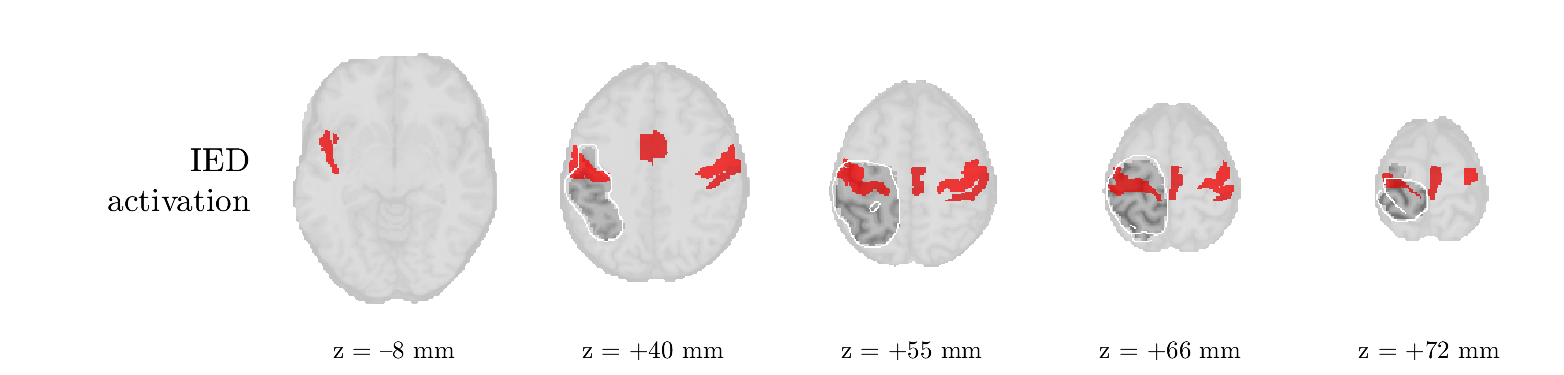

Patient 2

We analyze the solution with sources, and show the results in Figure 3 and 4. As for patient 1, we found a source which is strongly correlated to the MWF envelope, and which had a mostly low-frequency behavior characteristic for spikes. The topography is mostly uninformative, and does not clearly correspond to the patient’s clinical data. The third source is mostly present at both sides of the head, is very sparsely active in time, and has a high-frequency content: this is most likely an artifact due to the neck muscles. Again, there is one of the highest-entropy HRFs which belongs to a ROI in the IOZ. Now, the waveform is clearly resolved from the other HRFs, through the strong initial dip (before 0 seconds). Such a dip is sometimes observed in HRFs, but its underlying physiological mechanism is not yet fully understood. It is possible that this dip reflects altered vascular autoregulation near the IOZ (cfr. the explanation in the Section 1 of the main text), or a rapid depletion in oxygen due to IED generation (before the IED becomes visible on the EEG). Figure 4 furthermore shows that the IED-related component is significantly active in parts of the IOZ, and deactive in others. As mentioned earlier, this deactivation may or may not be due to errors in sign correction. Interestingly, the ROI with the high alteration in neurovascular coupling is distinct from both the activated and deactivated ROIs.